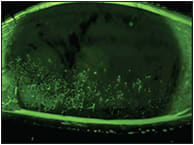

At every follow-up visit, the patient showed steady improvement in both signs and symptoms. By one month, we saw a dramatic improvement in corneal health (Figures 1 and 2). It was after two months of wear that she described her symptoms as being more than 90% improved.

Figure 2. Our patient’s cornea after approximately one month of scleral lens wear.